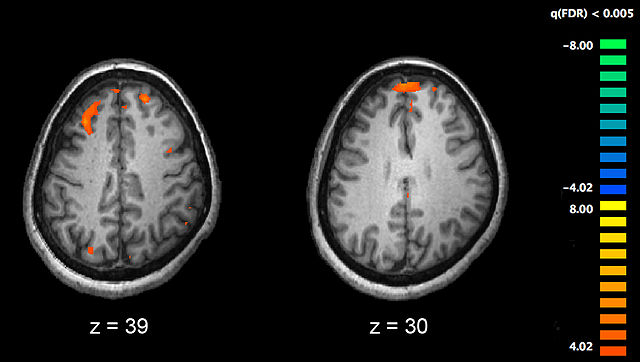

English: Image showing brain areas more active in controls than in schizophrenia patients during a working memory task during a fMRI study. Two brain slices are shown.

| Source |

PLoS One. 2010 Aug 11;5(8):e12068. An event-related FMRI study of phonological verbal working memory in schizophrenia.doi:10.1371/journal.pone.0012068.g002. PMID 20725639 |

Kim J, Matthews NL, Park S. |

Cropped from the full original image, leaving only the substraction between patients and controls. All p-values are corrected with false discovery rate of q<0.005.